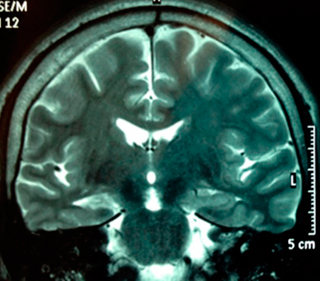

• Imagen de resonancia magnética con protocolo para cirugía de epilepsia: Se ha demostrado ser el procedimiento de neuroimagen estructural más sensible y específico en pacientes con epilepsia parcial. Las técnicas óptimas en adultos con epilepsia parcial incluyen imágenes coronales u oblicuo-coronales usando secuencia T1 y T2.